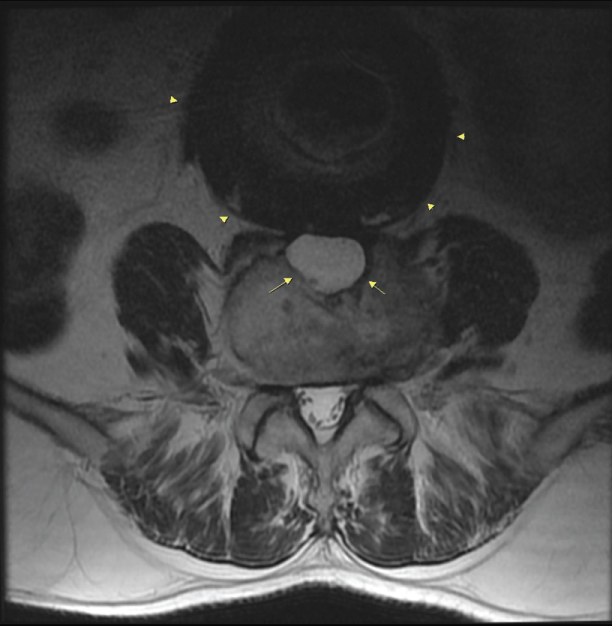

Case 2: A 80-year-old man was under follow up assessments due to deteriorated general health status after the failed operation for AAA. The chronic contained ruptured aortic aneurysm (CCAA) and erosion at the anterior corpus of the adjacent vertebra were established with CT (Figure 3 and Figure 4).

Figure 4: Axial CT image shows that chronic contained ruptured aneurysm with bilateral paravertebral hematomas (arrow heads) and also cortical erosion (long arrow) on the contact surface of this vertebras. View Figure 4